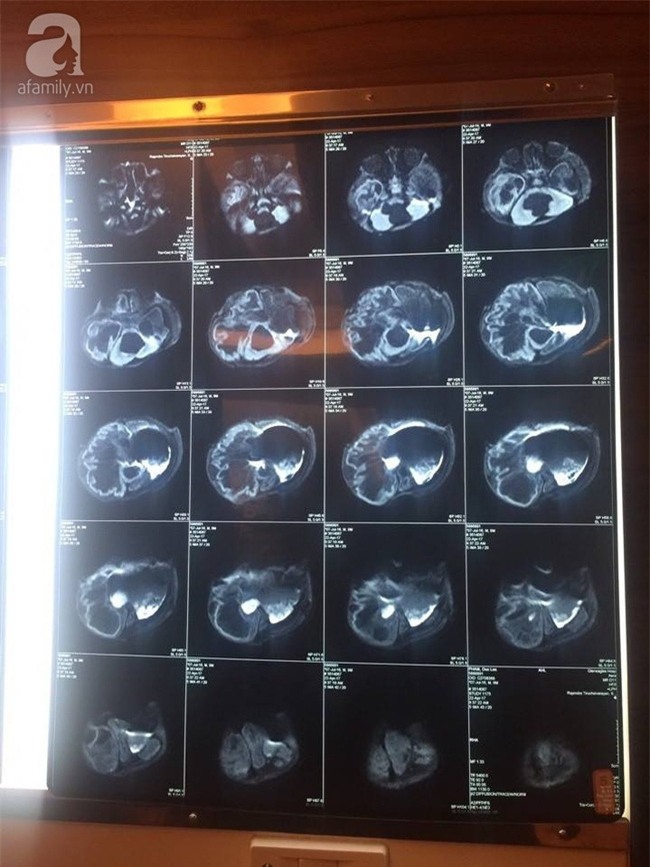

![]() Ảnh chụp phim lúc vừa nhập viện. ![]() Và ảnh chụp phim sau khi điều trị cho thấy não của bé Lộc đã có dấu hiệu phát triển. |

Trước đó vào ngày 9-5, trên trang chính thức của chùa Vạn Đức cũng đã phát đi thông tin bé Lộc đã được tập sữa bằng muỗng và sắp tới sẽ được cho ăn dặm, vì em đã bắt đầu lớn. Bé cũng đã có thể tự bú bình (mỗi ngày khoảng 300ml). "Con đã được chụp MRI lại, kết quả rất khả quan, mủ trong não đã giảm hẳn, khu vực bị nhiễm trùng đã giảm đáng kể, và não con có không gian để phát triển thêm" - nhà chùa cho biết.